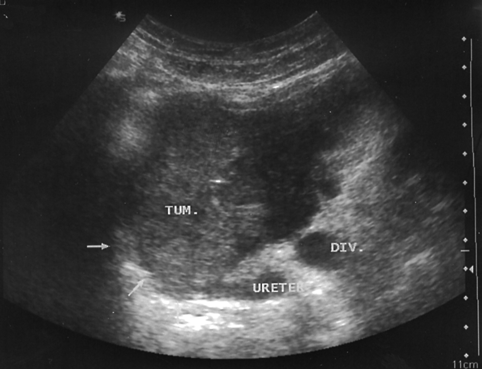

Рисунок 3. Рак мочевого пузыря, стадия T4

УЗТ мочевого пузыря в поперечной плоскости. Опухоль располагается в области шейки пузыря. Стрелками указана инфильтрация предстательной железы